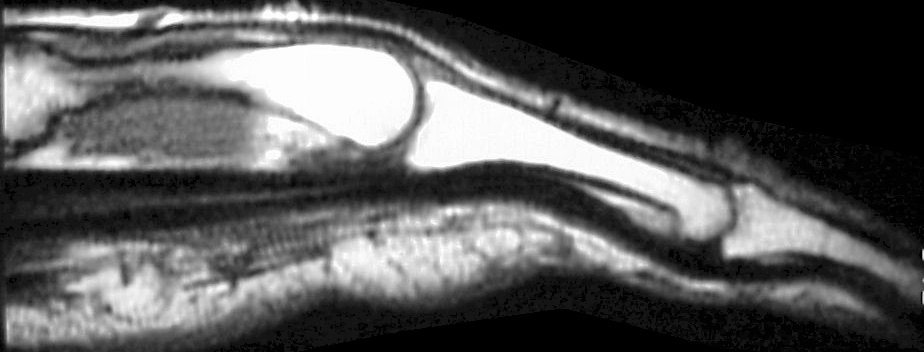

Mild wrist stiffness prevented adequate visualization of the hook of the hamate with plain films. Plain films of the finger were normal for age. Further evaluation was obtained with MRI. Flexor tendon signals in the finger were normal:

Click for larger image